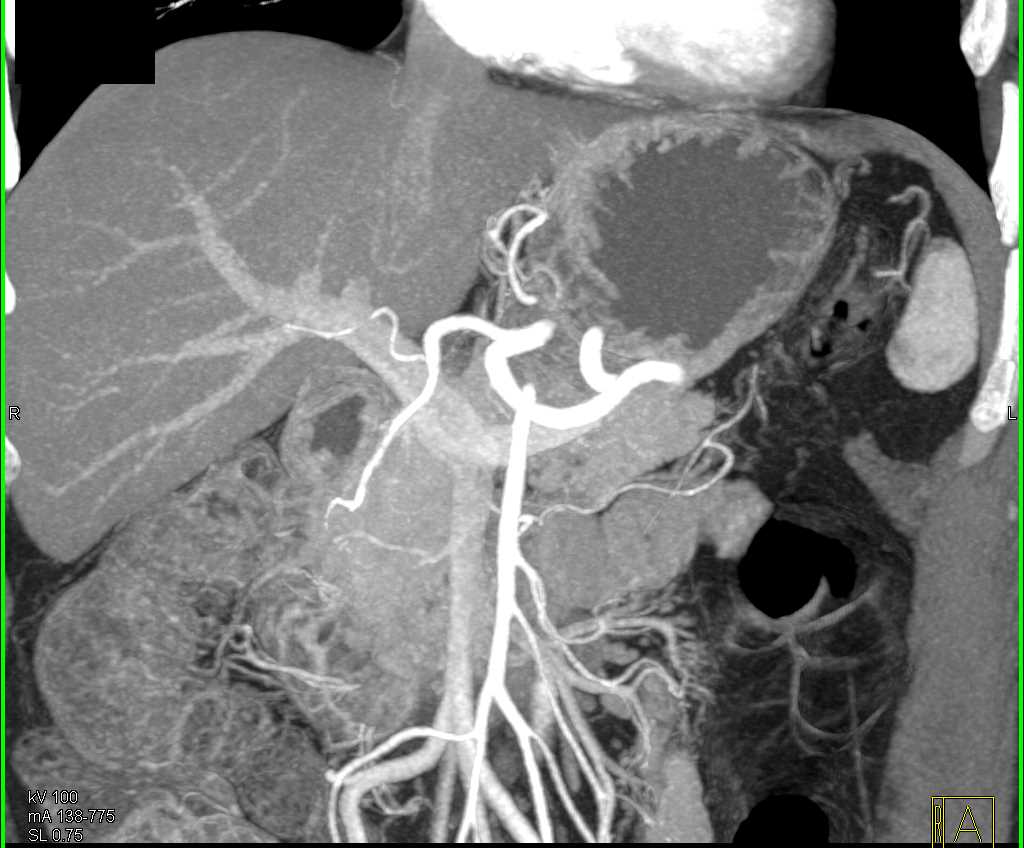

Duodenal Carcinoma with Obstruction